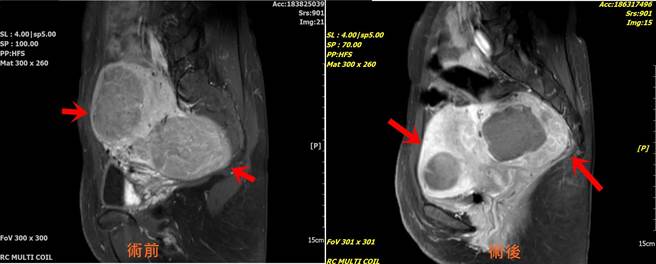

病人接受的治疗不用麻醉、轻松且舒服地进行,3天后就完成海芙刀治疗,术后不到3个月,原本经血量多、头痛与腰酸症状有明显改善,术后5个月进行MRI磁振造影检查,发现两颗肌瘤都明显缩小超过3公分,月经经期变规律、经血量恢復正常、血块的情况也几乎没有,经期来时伴随的头痛与腰酸状况都不再出现,连腹部整个都缩小了一圈。